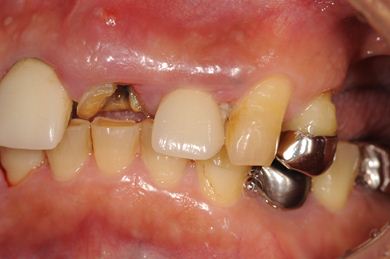

| 性別/年齢 | 男性 / 58歳 | ||||||||||||||||||||||||||||||||

| 主訴 | 上前歯欠損部のインプラント治療を希望。 | ||||||||||||||||||||||||||||||||

| 治療方針 | 右上奥はソケットリフトにて上顎洞拳上してインプラント埋入を可能にし、上顎前歯部は骨再生法によりインプラント治療を行う。その他、補綴により口腔内全体の機能的審美的回復を行う。 | ||||||||||||||||||||||||||||||||

| 治療内容 | インプラント8本(GBR、ソケットリフト)、ハイブリッドセラミッククラウン17本(セラミック用土台5本) | ||||||||||||||||||||||||||||||||